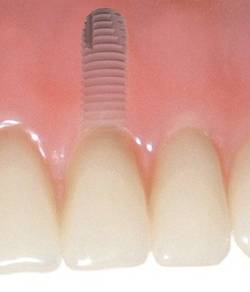

Zubní implantáty jsou umělé zubní kořeny.

Jsou zavedeny do kosti horní nebo dolní čelisti a umožňují náhradu jednoho, několika či všech zubů pomocí korunek, můstků, které jsou na ně připevněny nebo tvoří podporu pro zubní protézy.

BEGO Semados ® implantáty jsou vyrobeny z čistého titanu - materiálu, který je plně akceptováno v lidském těle, jejichž povrch má speciální úpravu

TiPurePlus pro bezpečnější, rychlejší a kvalitnější hojení.